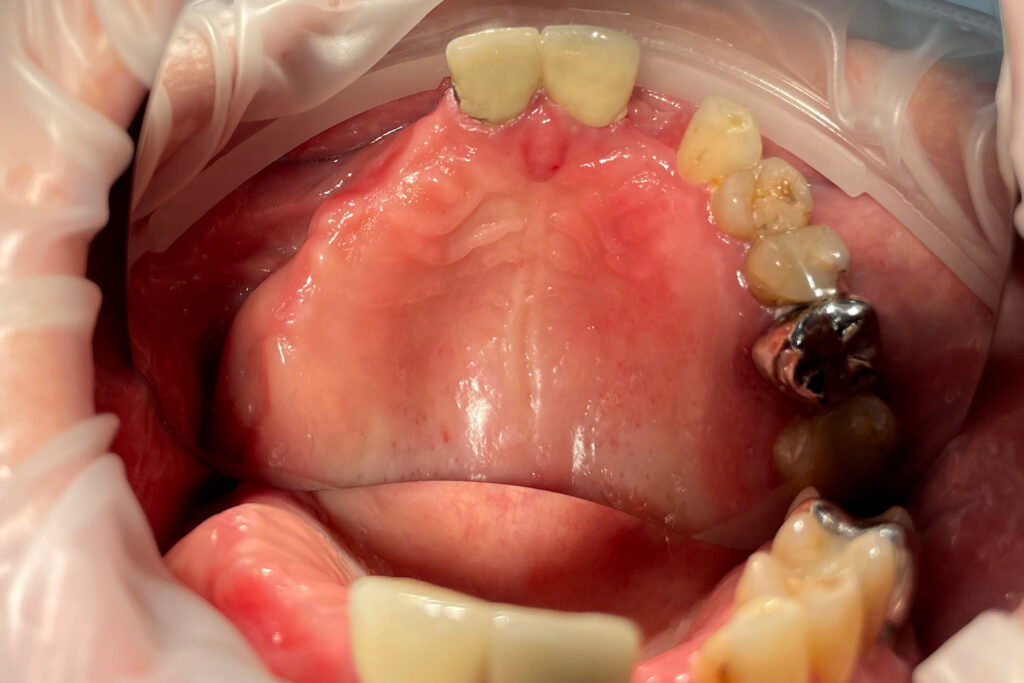

Ситуация до лечения

Жалобы: Пациент обратился к нам с целью проведения комплексной имплантации верхней челюсти.

Диагноз: Частичная вторичная адентия верхней челюсти.

После консультации было принято решение об удалении зубов на верхней челюсти, которые находились в неудовлетворительном состоянии

и проведении комплексной имплантации по системе All-on-4.